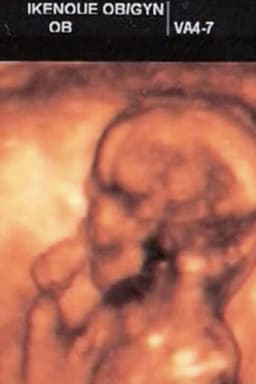

Yuri Muraoka was born in Tokyo in 1981. Dropped out of the high school attached to Japan Women's University, graduated the 26th class of Image Forum Institute of the Moving Image. Continues to create moving images and photographic works of "self-portraiture". All of her works are self-created and self-performed. Mother of two children.